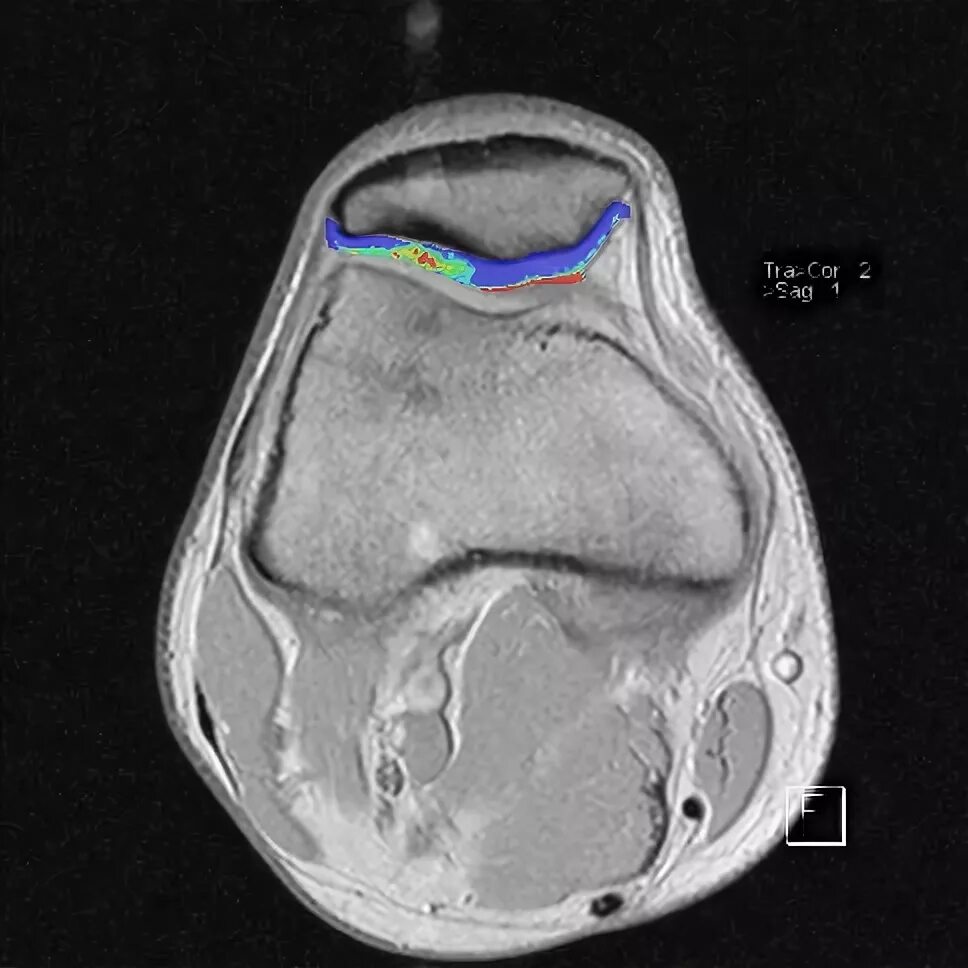

Повреждение хряща по outerbridge